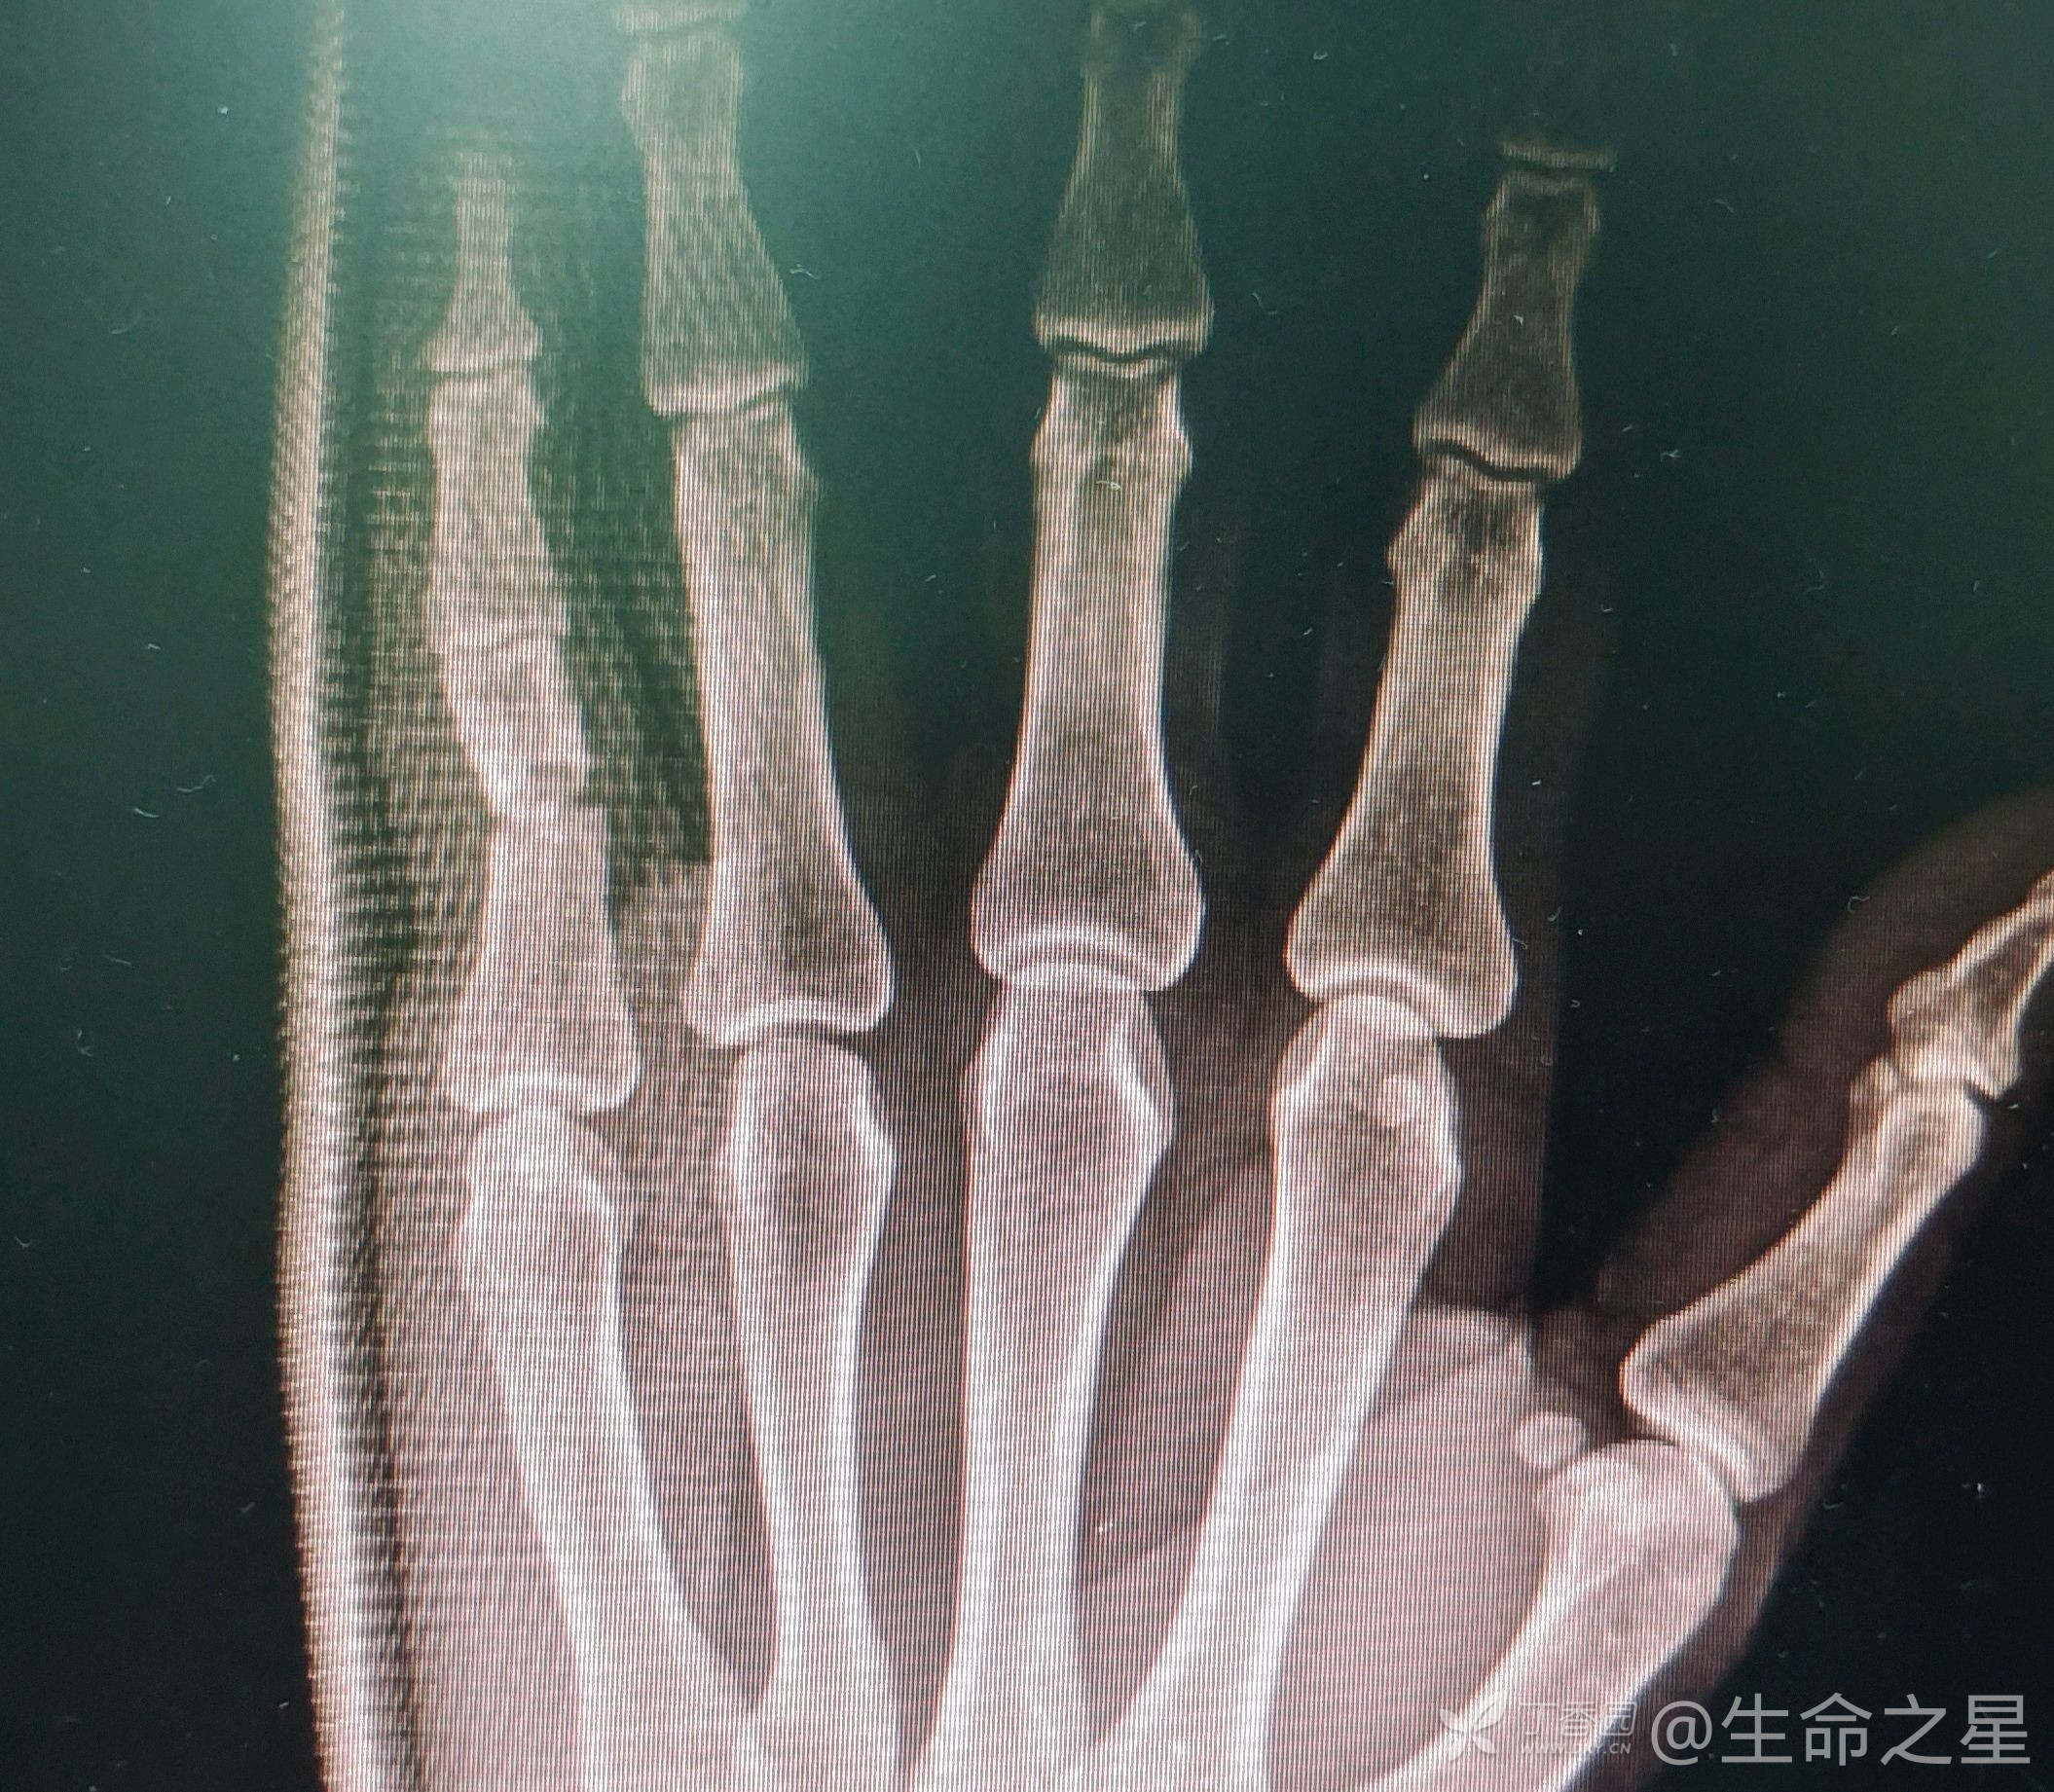

zzf1056 达人已点赞中年男子,重物砸伤致小指疼痛畸形半月余,既往外伤时拍片提示小指近节指骨骨折成角,建议手术,患者拒绝,2周后再次来门诊就诊,收入院

行手术内固定治疗。